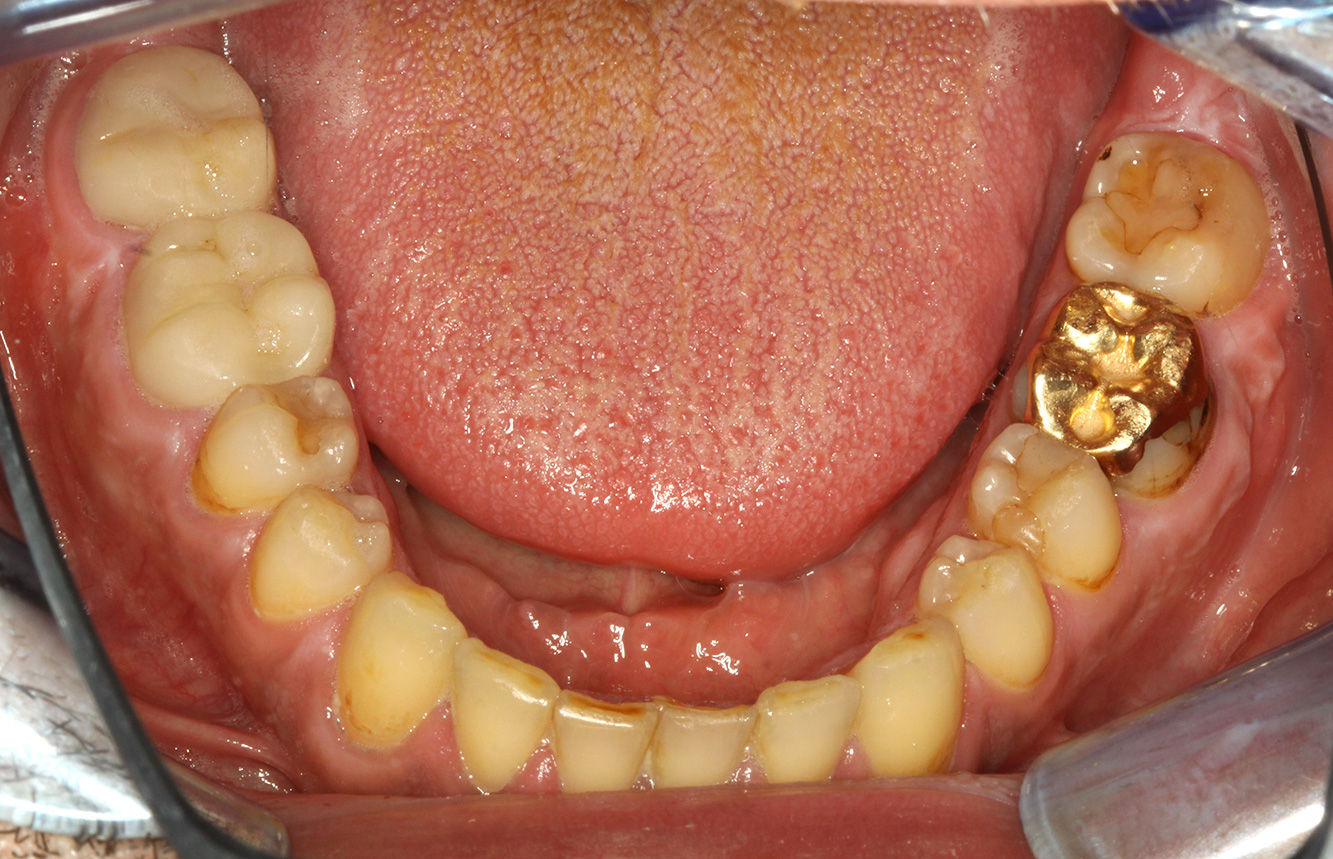

The healthy patient with early periodontal disease

The 68-year-old patient has no general health conditions and is not taking any medication that may be relevant to her oral health, and her lifestyle does not pose any particular risk. The patient has two dental implants (3rd quadrant, for five years) and a previous case of periodontal disease (stage IV, grade B periodontitis) with tooth loss. Currently the periodontal conditions are stable. However, periodontitis significantly increases the biological complications of implantations and there is a risk of implant loss (21). Four recommendations can be determined for the prophylaxis session. more